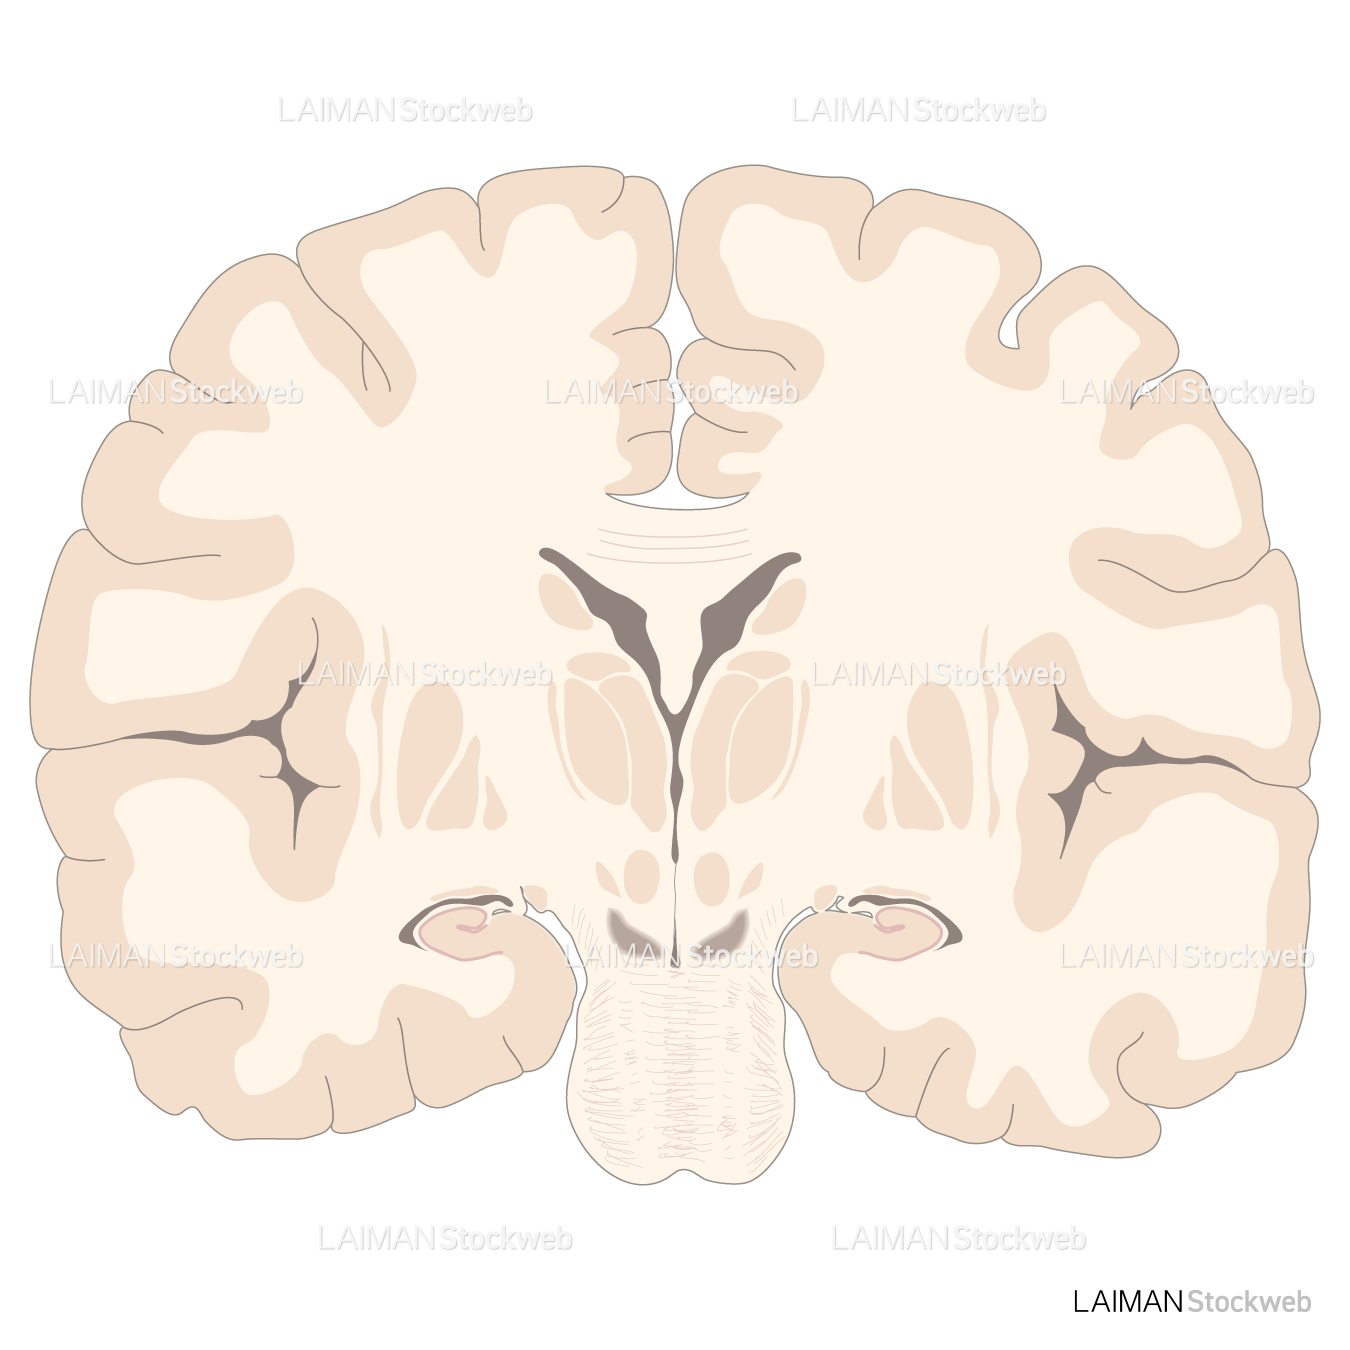

大脳 冠状断面<< 神経系 << バイオメディカル CG ライブラリー << 株式会社メタ・コーポレーション・ジャパン。

大脑冠状面和矢状面结构分解图PNG图片素材下载_图片编号2533656-PNG素材网。

经下丘冠状面层面 枕颞沟呈“11”型,白色实线为枕颞沟,红色实线为侧副沟。